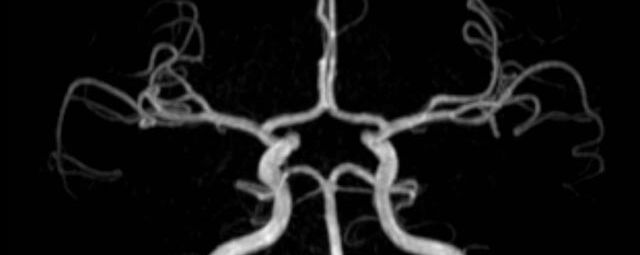

Kopf/Hals

Kopf

• akute Schlaganfalldiagnostik und chronische Durchblutungsstörungen

• entzündliche Prozesse des Gehirns oder der Gesichtsweichteile

• Tumore, ggf. mit Spektroskopie

• Abklärung Schwindel, zentrale Sehstörung, Kopfschmerz

• Metastasenverdacht

Halsgefäße

• Multiple Sklerose

• Abklärung Hirnnerven, Schädelbasis inkl. Hypophyse

• Abklärung Kleinhirn, Hirnstamm, Halsmark

• intrakranielle Gefäße (Abklärung Verschluss, Stenose, Aneurysma)

• Halsgefäße zur Therapieplanung (z.B. Stent, Operation)